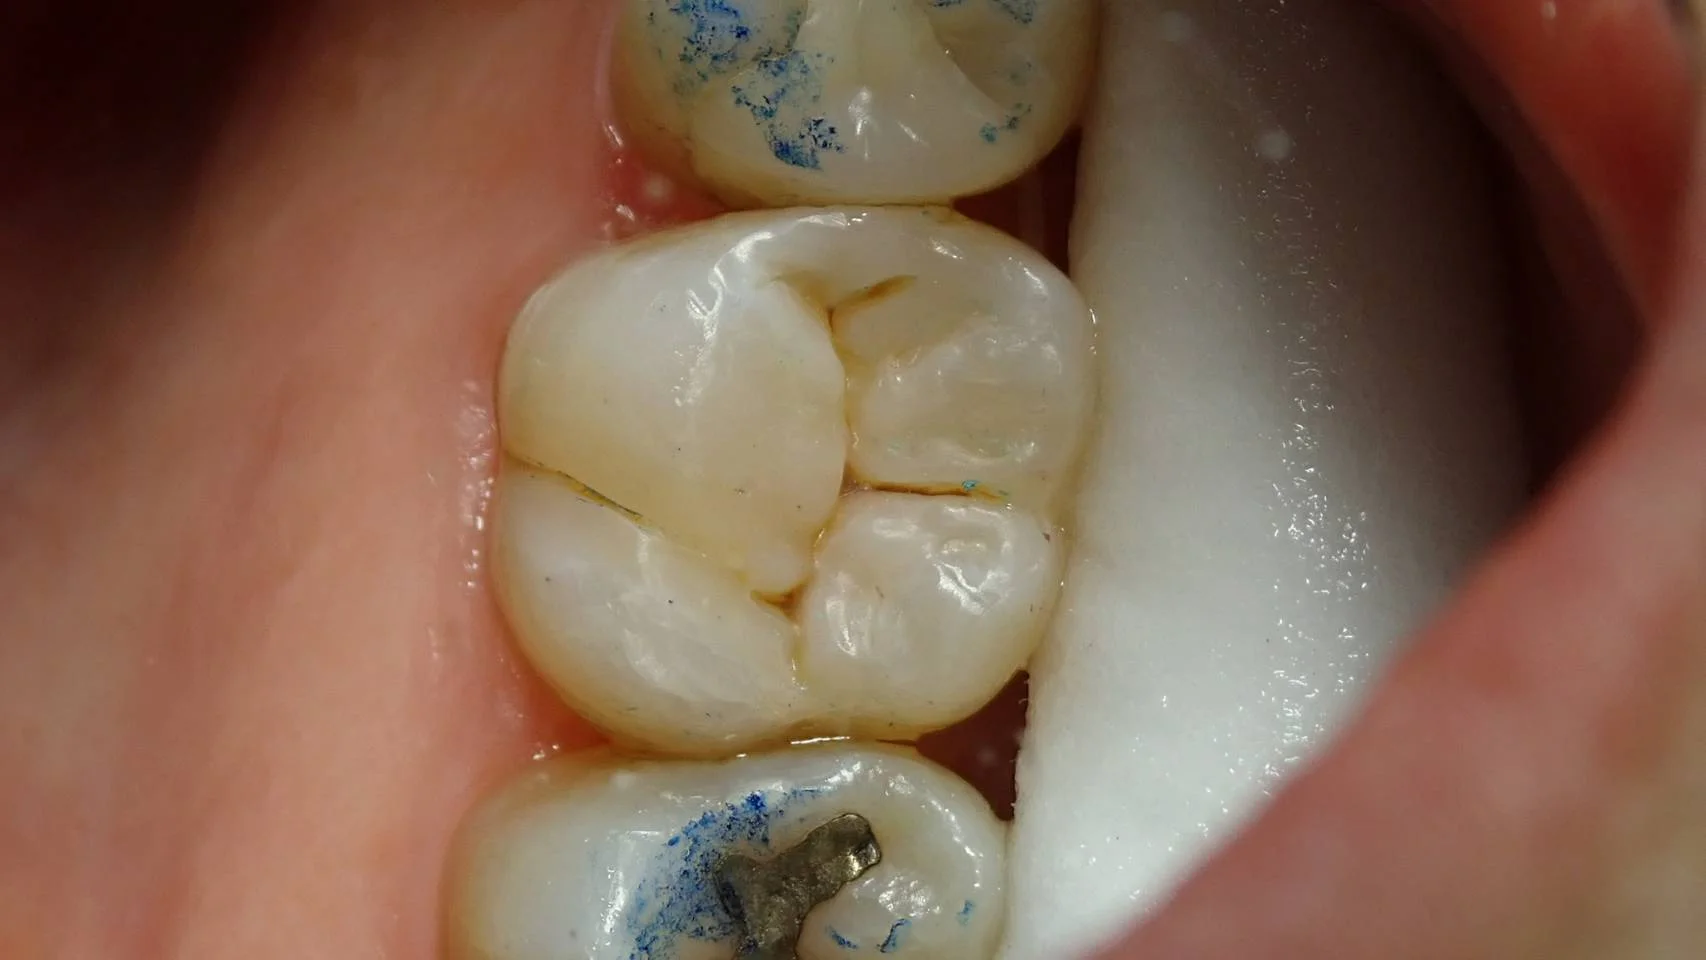

そして、術後、かみ合わせを合わせた状態がこちらです。

想像よりもかみ合わせが深く、一部折角付けたステインを削る必要が出てしまいました・・・。

本来ならかみ合わせの調整がいらないように詰められれば一番良いのですが・・・現在の私の力量ではまだそこまではいけません。 ただ、それでも調整する量は比較的少なく済んでいることが多いとは思います。